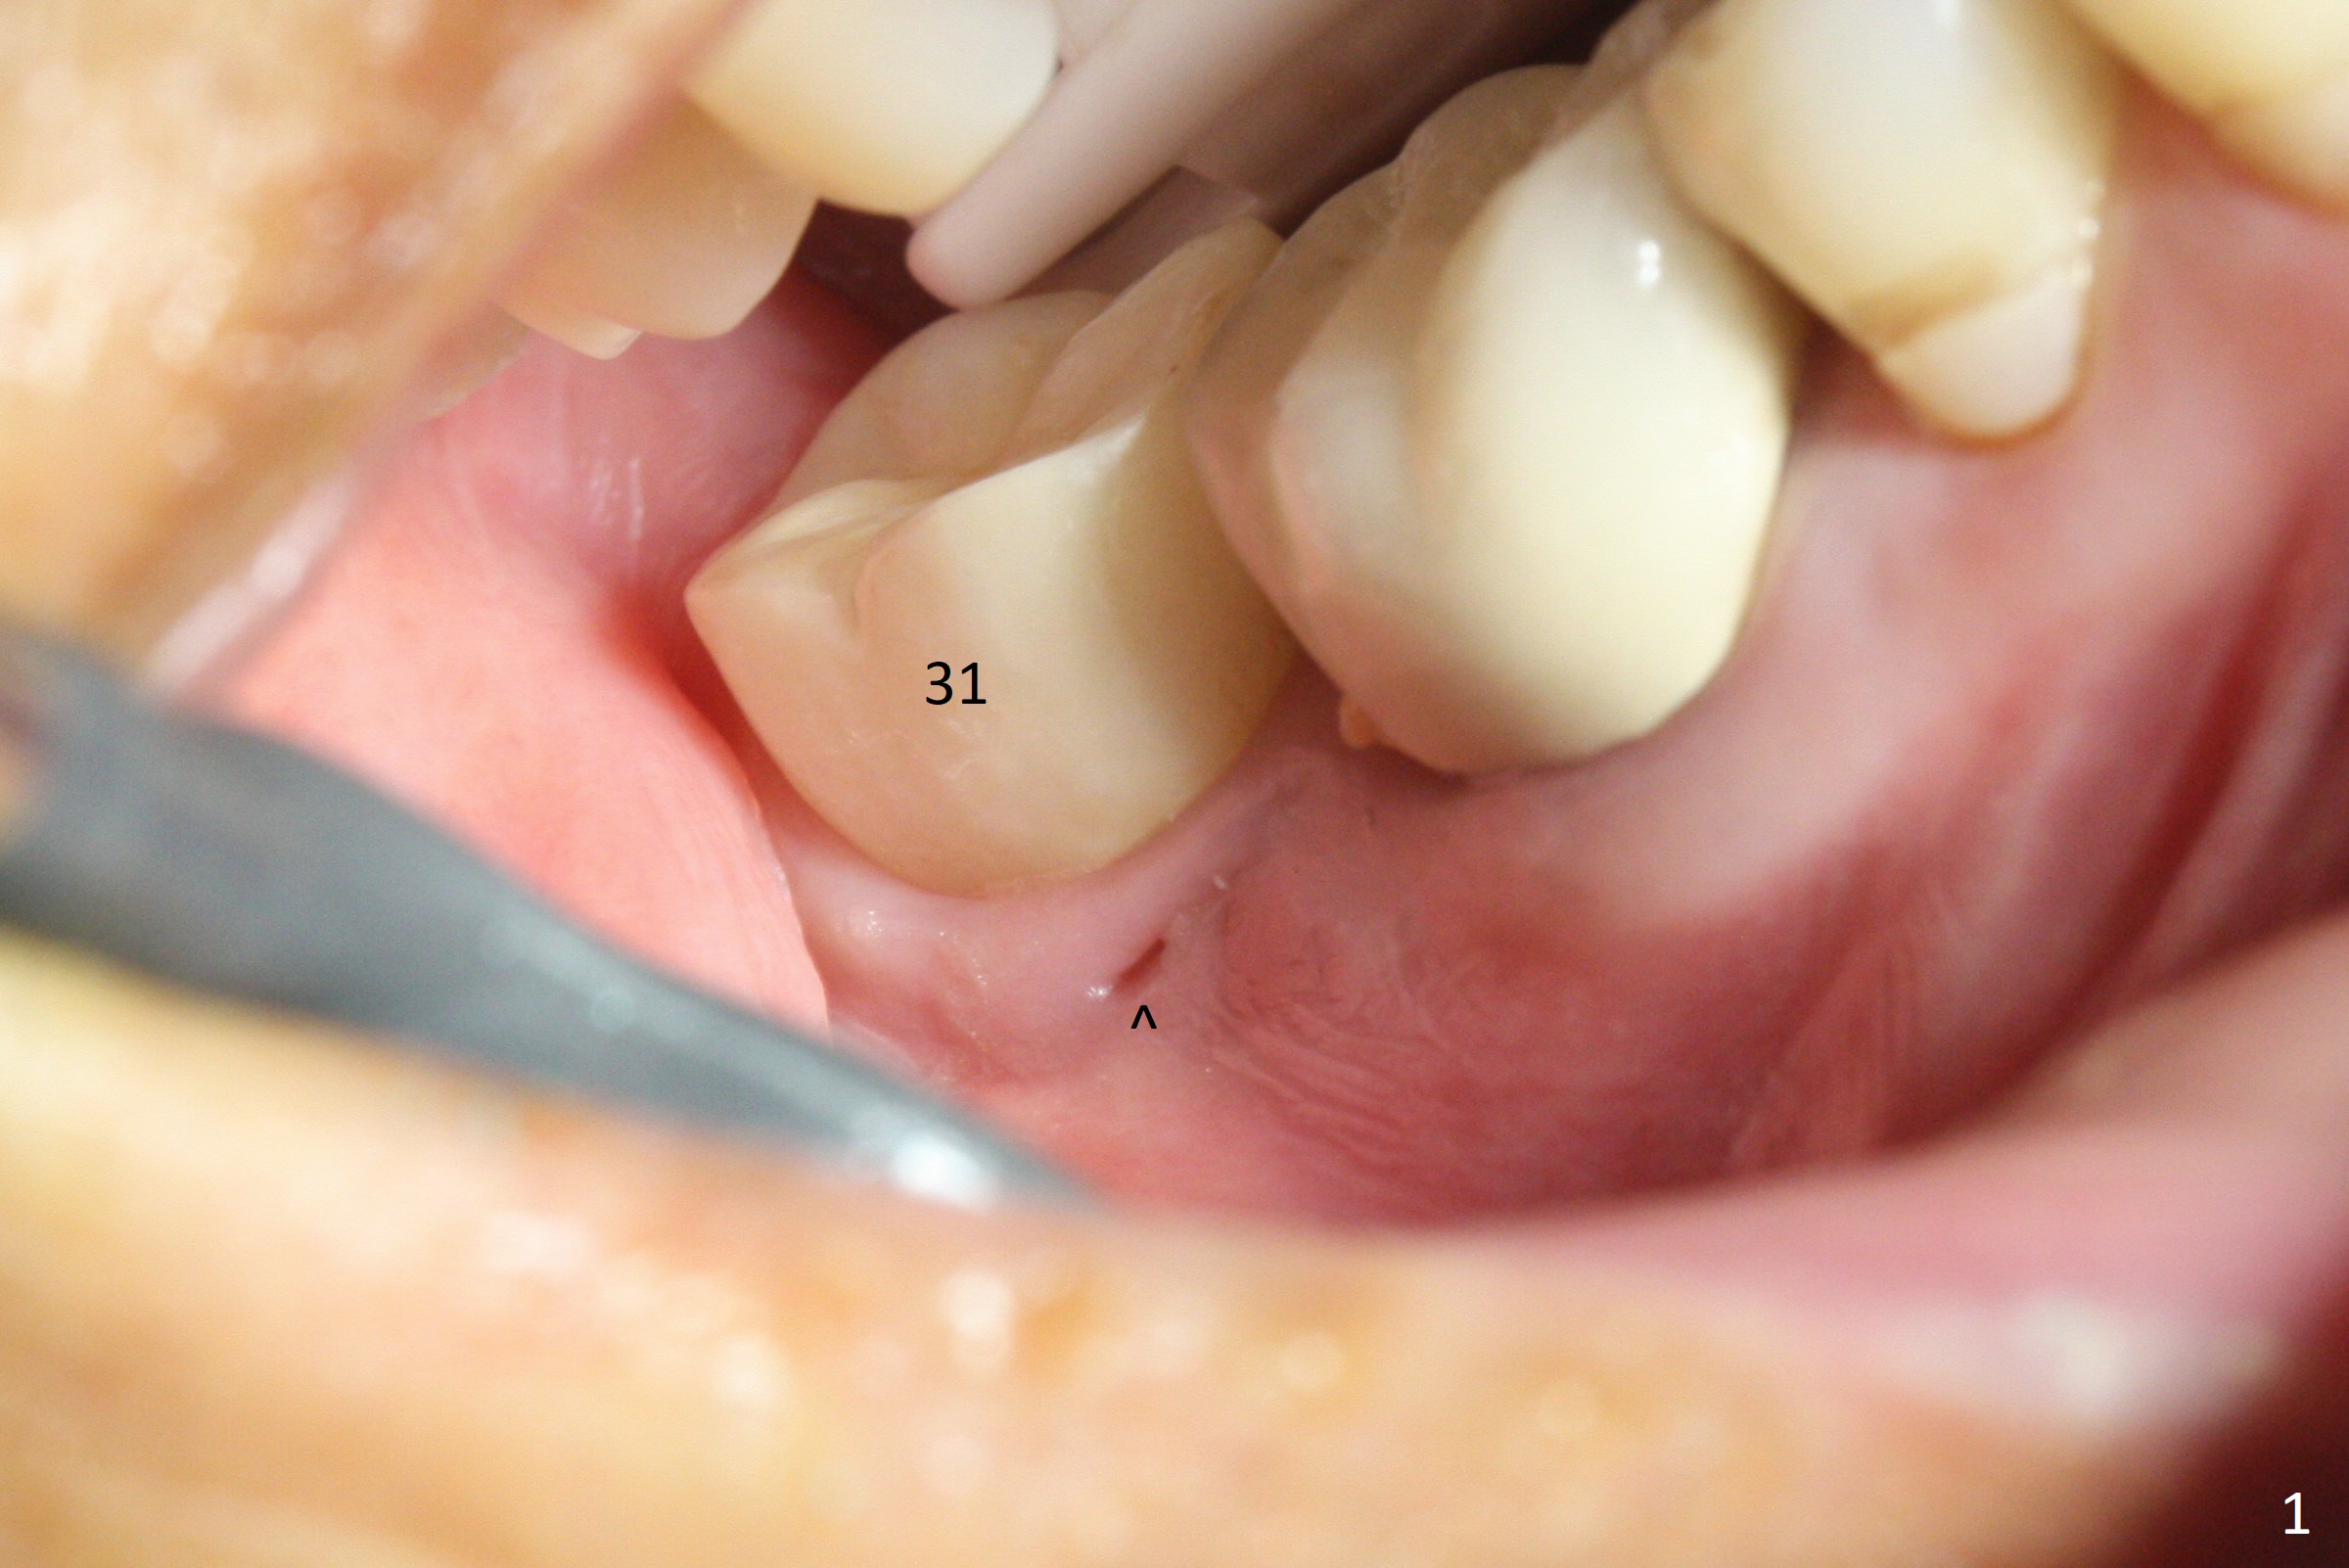

There is a mesiobuccal fistula at #31 with periimplantitis (Fig.1 ^). The bone loss is severe before and after implant removal (Fig.2). It is impossible to place bone-level implant in the original osteotomy due to insufficient bone height. There is pain when a new osteotomy is being initiated in the mesial slope. Following placement of Vera Graft (Fig.3), collagen plug and 6-month resorbable membrane, the wound is closed with suture (mild tension). Postop, there is oozing. Periodontal dressing should have been applied. If the ridge can be preserved in 4-6 months, a 11 mm long implant (Fig.4 green line with 4 mm of the native bone) can be placed with 1.9 mm clearance (red dashed line: the superior border of the Inferior Alveolar Canal); the abutment is estimated to have 4 mm cuff (pink). The socket appears to be healing 8 days postop (Fig.5). The ridge remains wide 5 months post implant removal, although the bone density is low (Fig.6,7 (still ~ 1000 units). It seems that a 5x11.5 mm implant could be placed in the mesiobuccal aspect of the bony defect (Fig.8). For better occlusion, the implant should be shorter (5x8.5 mm) after discussion with the guide lab (Fig.9). Make sure that the most coronal thread is buried by the bone graft, i.e., underneath the crest(>).